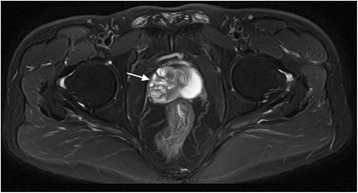

The current report presents the case of a 42-year-old male with extraordinarily salient urination difficulty that had lasted 6 months. Transrectal ultrasonography and pelvic magnetic resonance imaging demonstrated prostatic hyperplasia and cyst. PSA level was 20.65 (>4) μg/L in the patient. Transrectal prostatic biopsy revealed benign prostatic hyperplasia. He agreed to receive plasmakinetic resection of the prostate. During operation a lobulated lump was unexpectedly found on the verumontanum, with the prostate macroscopically normal. Complete tumor excision was performed and pathological assessment indicated phyllodes tumor of the verumontanum. The patient had an uneventful post-operative course and recovered well. The diagnosis, histological classification, treatment, and prognosis of this case are presented. It is necessary to perform cystoscopy to exclude verumontanum tumor even when all imaging examinations indicate prostate hyperplasia, especially in young males. Virtual slides: The virtual slide(s) for this article can be found here: http://www.diagnosticpathology.diagnomx.eu/vs/1868931661161758.